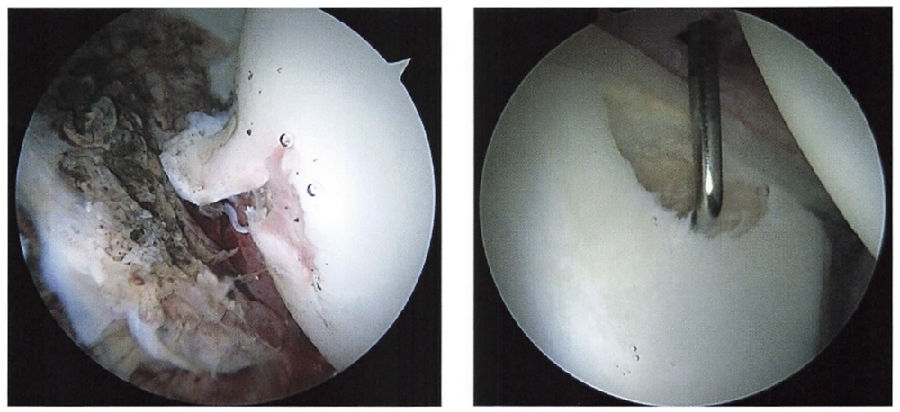

后外侧入路

位于大转子顶点后上方1cm。后外侧入路穿过臀中肌和臀小肌,到达髋关节后外侧关节囊,最靠近的神经血管结构为坐骨神经(图51-69C)。后外侧入路可以观察中间室,修复后方盂唇(图30-7)。

图51-69C 标准入路:后外侧入路

图30-7 A.70°镜头下后外侧入路观察,可见左侧为髋臼窝,右侧为股骨头及其剥脱的软骨;B.可见中前入路进入的探钩,可见缺损的髋臼软骨,上盂唇完整,右侧为股骨头